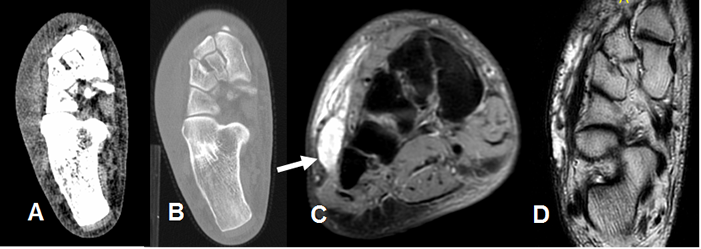

En casos de lesión de la sindesmosis tibioperoneoastragalina, se produce ruptura de los ligamentos interóseos (Tibioperoneo anterior y posterior). En la Rx se observa aumento del espacio entre la tibia y el peroné mayor de 6 mm, en la proyección AP. (12). (Fig 59 A y 59 B). En las Rx de stress puede haber aumento de los espacios articulares, en casos de lesiones ligamentarias completas. (Fig 59 C y 59 D).

Fig 59. Lesión de ligamentos de la mortaja tibioperonea.

A: Rx AP. Aumento del espacio tibioperoneo, por lesión ligamentaria.

B: TAC axial. Aumento del espacio tibioperoneo posterior, por lesión ligamentaria.

Fig 59 B. Lesión de la mortaja.

A: Rx AP. Fractura no desplazada del peroné distal. Se aprecia incremento del espacio articular tibio peroneo distal y subluxación de la articulación tibioastragalina, por lesión ligamentaria.

B: Rx AP. Cambios PostQx con reducción de la subluxación y estabilización de la fractura en el peroné.